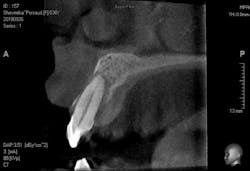

Another scenario that took place in a private practice with actual dollar amounts can be seen in treatment plan C. This patient had already paid for treatment plan B in the $5,000–$7,000 range and subsequently presented to the practice with moderate peri-implantitis. In addition to the money the patient had already invested, she would now be responsible for the financial costs of treatment plan C.

After reviewing the additional costs and lengthy healing time involved with surgery to correct the ailing implant, the overall costs associated with treatment were in the $8,000–$10,000 range, with more than three years of treatment time invested. Of important note is that most insurance companies limit the amount of reimbursement for implant-related services. When dealing with insurance companies, accurate ADA coding and claims submission are critical to facilitate services and expedite reimbursement.